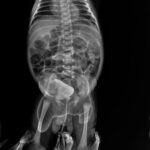

Here is a case of Chyluria from Sitapur. He suffered since March 2020 with milky urine disease, and his condition was getting worse day by day. As with most Chyluria cases, protein leak and fat weaken the body day by day, and weight loss is common. As the condition was not resolving with the allopathic medication with a famous urologist, there were clots in the urine, and later blood clots start appearing in the urine. He was finally told for the surgical intervention as endoscopic instillation of Betadine or Silver nitrate in the kidney. We started his treatment with our exclusive mode of treatment by medicine transmission through hair. On the third day of the start of the treatment, his chyle never appeared in the urine. He told us that he started taking the fat in the diet without any discomfort in the follow-up calls. We have taken his follow-up even we stopped the treatment from our end, but his problem never appeared again.